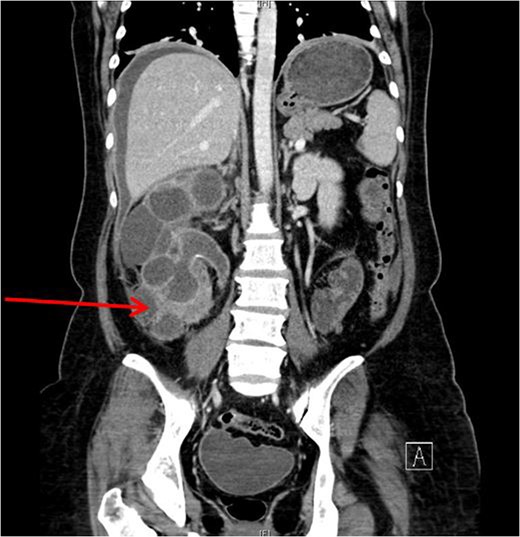

Xanthogranulomatous pyelonephritis (XGPN) is a rare form of chronic pyelonephritis with progressive loss of renal function. Commonly, obstructing urinary calculi are seen. It is difficult to differentiate between XGPN and malignancy in many cases, and the diagnosis is usually only confirmed post-operatively upon histopathological examination of the specimen. Surgical treatment is often the main treatment modality due to suspicion for malignancy. Here, we present a case of XGPN that presented with abdominal distension, which was eventually discovered to be due to a preperitoneal abscess.

She underwent insertion of a right percutaneous nephrostomy drain, percutaneous drainage of the anterior abdominal collection, as well as a percutaneous biopsy of the right renal soft tissue lesion. Urine cultures from the percutaneous nephrostomy grew Proteus mirabilis. Fluid cytology from the abdominal collection showed acute inflammatory cells. Biopsy of the renal lesion showed xanthogranulomatous inflammation.

After a period of antibiotic treatment, she underwent open right nephroureterectomy with exploration, drainage and washout of the preperitoneal collection. During surgery, 1 l of pus was drained from the preperitoneal space, and cultures grew P. mirabilis. The ureter was ligated below the level of the calculus and removed together with the kidney. Final histopathology results showed XGPN with no evidence of malignancy in the kidney or peritoneal lining.

Our patient had an atypical presentation with abdominal distension and presumed ascites, which was eventually revealed to be an anterior preperitoneal collection secondary to infection. Although the initial suspicion was that of a malignant process complicated by ascites, subsequent cytology and histopathological results showed that it was likely benign. In view of the non-functioning renal unit and significant abdominal collection, she underwent definitive surgery.

The most common urinary pathogen identified was Escherichiacoli [3], and common areas of involvement were the retroperitoneum and psoas muscle. In our patient, the retroperitoneal space was surprisingly not greatly involved, but rather it was the anterior preperitoneal space that had significant adhesions and inflammation. The pathogen identified from both nephrostomy and preperitoneal collection was P. mirabilis, showing that both pathologies were linked.